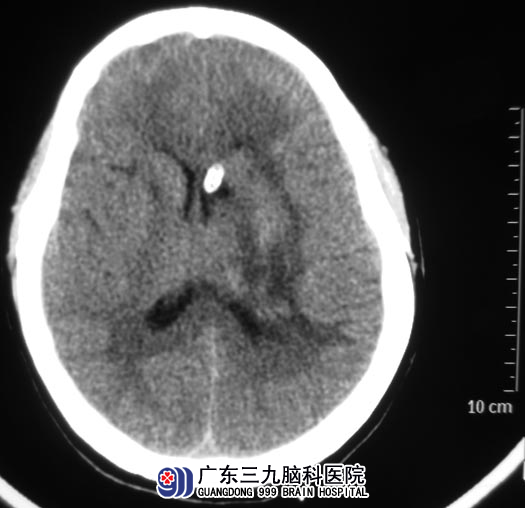

广东三九脑科医院头颅CTA检查提示:左侧基底节区脑出血破入脑室,未见动脉瘤或动静脉畸形。综合神经外科 鲁明主任建议立即手术治疗,全麻下行左侧基底节区脑出血钻孔引流+侧脑室穿刺外引流术;术后复查CT显示脑内血肿明显减少,血肿内给予尿激酶鞘内注射溶血凝块。

一周的治疗后,李姐由昏迷状态逐渐清醒。早期语言、肢体活动等康复手段介入。十天后复查CT示原左侧基底节区血肿基本吸收。四周后出院时,她神志清醒,能在家人的扶持下缓慢行走。

▲手术后